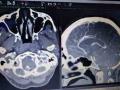

नागपूर :मेंदूच्या दुर्मिळ आजारावर यशस्वी शस्त्रक्रिया : महिलेला मिळाले जीवनदान

मेंदूतील रक्तवाहिन्यांवरील फुग्याच्या आजाराला वैद्यकीय भाषेत ‘अ‍ॅन्युरिजम’ म्हटले जाते. हा दुर्मिळातील दुर्मिळ आजार आहे. यावर तातडीची शस्त्रक्रिया हाच पर्याय असतो. अत्यंत क्लिष्ट व गुंतागुंतीच्या या शस्त्रक्रियेदरम्यान जीवहानी किंवा अपंगत्व येण्याचा ...